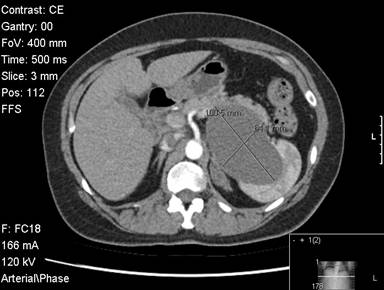

A fifty-two-year-old female was evaluated for abdominal pain. She had a vague history of upper and left sided abdominal pain for 6 months. An ultrasound showed a cystic lesion in the left upper abdomen. A CT scan subsequently confirmed the presence of a large 10 cm cystic lesion in very close proximity to the spleen and the pancreas. The lesion reached close to the neck of the pancreas. The lesion involved the mid-body / tail of the pancreas, was abutting against the spleen (Figures 1 and 2). There was close proximity to the splenic vein, although the vein was patent. The splenic artery was close but seemed uninvolved (Figure 3). The cyst wall was uniform. There were no internal septations or any other features to suggest an intracystic solid component or bleeding. There were no calcifications with the cyst. The rest of the pancreas appeared normal with no evidence of pancreatitis. There were no gall stones or any other biliary abnormality. Clinicoradiologically it was felt to be a large cyst possibly a splenic cyst. However given the fact that she was symptomatic, we decided to proceed with a laparoscopic resection. All her blood tests including tumour marker profile (CA 19-9 and CEA) were normal. She underwent a laparoscopic distal pancreatectomy with splenectomy. At laparoscopy we discovered a large cystic lesion occupying the lesser sac and abutting against the spleen. The pancreas could not be separated off the cyst. We completely mobilised the stomach off the cyst and the pancreas, to completely expose the pancreas with the cyst in the lesser sac. We completed a distal pancreatectomy with splenectomy laparoscopically, with complete enbloc excision of the cyst (Figure 4). Post-operative recovery was uneventful and the patient was discharged 4 days following surgery. Gross pathology showed a 90x50x60 mm cystic lesion, attached to and arising from the inferior and posterior aspect of the pancreas. On pathology the rest of the pancreas appeared normal and the splenic capsule was not breached. The histology of the cyst showed the presence of pseudo stratified ciliated columnar epithelium , overlying some connective tissue (Figure 5; H&E, magnification x10) .Similar features were confirmed on the high powered images of the cyst wall as well (H&E, magnification x20). Based on these characteristic and rather unusual histological features, the diagnosis of a ciliated foregut cyst of the pancreas was established.

Figure 2. CT scan image showing the cyst within the body/tail of the pancreas. |